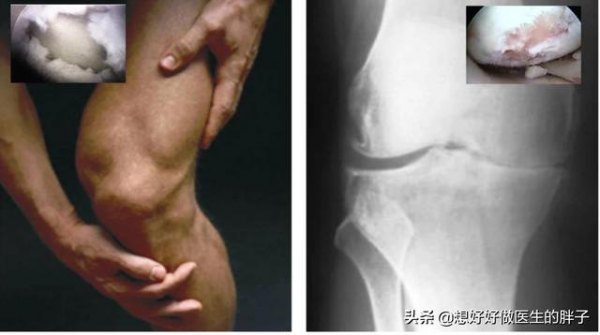

引起膝关节疼痛的关节炎有很多种,比如常见的有痛风性关节炎、骨关节炎、风湿或者是类风湿导致的关节炎,相信题主所问的应该是最常见的骨关节炎所导致的疼痛,因为这种关节炎可谓是最常见的一种导致关节疼痛的疾病了,这种疾病往往与朋友们所认为的骨质增生骨刺紧密相连,今天我们就来聊一聊这个问题。

骨关节炎的病理基础

骨关节炎的病理基础是我们关节腔内软骨的破损。当各种各样的原因,导致骨关节内的软骨出现磨损以后,就会出现关节的不稳定,而关节不稳定以后就会继发形成关节的骨赘,少量的骨髓人们并不会有特殊的症状,但是当骨赘形成的量比较多,形成的比较大,就会刺激到关节周围的软组织、神经或者是肌腱等结构诱发疼痛。而且当关节腔的软骨磨损过于严重以后,会造成关节间隙的狭窄,骨与骨之间会形成压力的改变,这也是导致疼痛的原因之一。